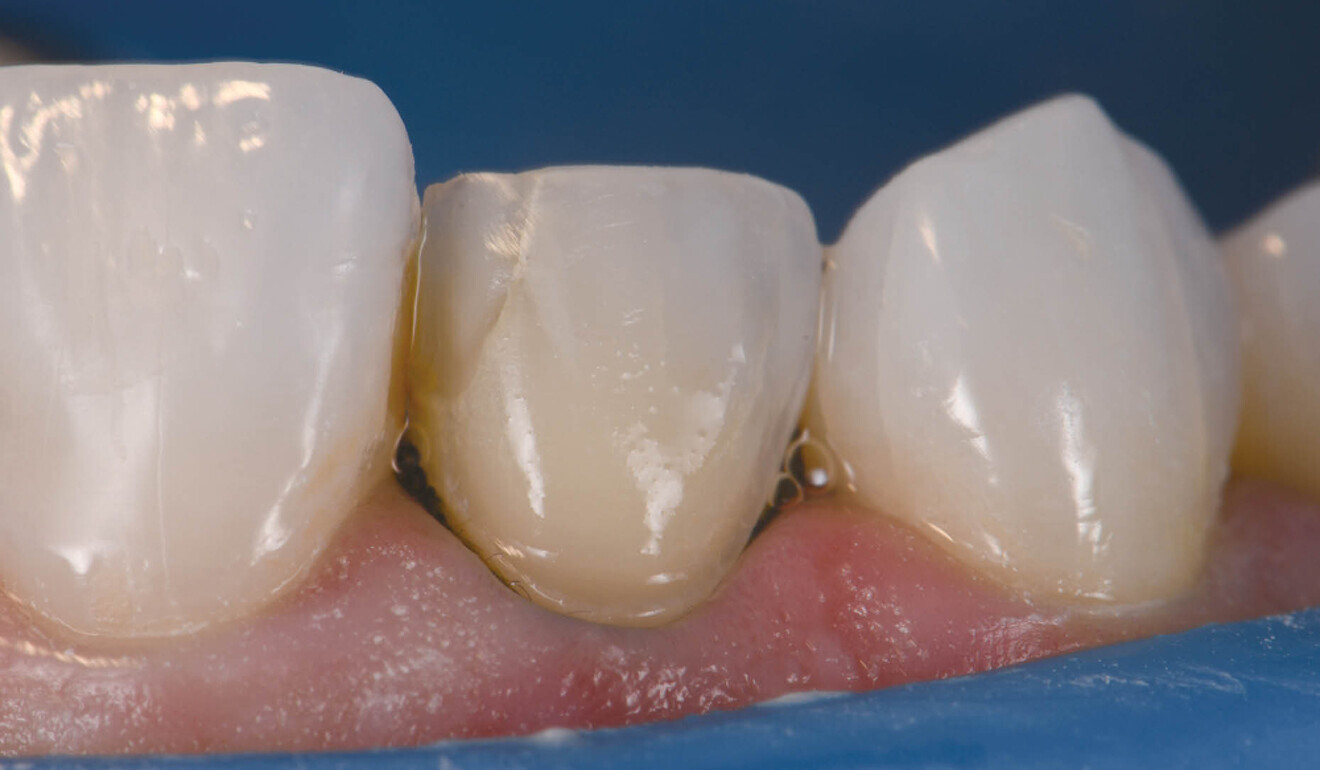

Fig. 6: PANAVIA Veneer LC immediately after seating. Note the viscous, non-slumpy nature of the cement, which allows for ease of removal under both wet and gel-phase options.

The cement was rendered into a gel state, which facilitated clumping or en masse removal of cement, requiring minimal clean-up (Fig. 7). The margins were coated using a clear glycerine gel prior to final polymerisation to eliminate the oxygen inhibition layer (Fig. 8). The margins were finished and polished to a high shine and the occlusion of the restorations verified. The postoperative views showed excellent aesthetic marginal integration (Fig. 9). On polarised photograph reassessment, the restorations were found to be well integrated into the new smile aesthetically and functionally (Fig. 10), and aesthetic augmentation of tooth #23 to match the contralateral canine was awaited.